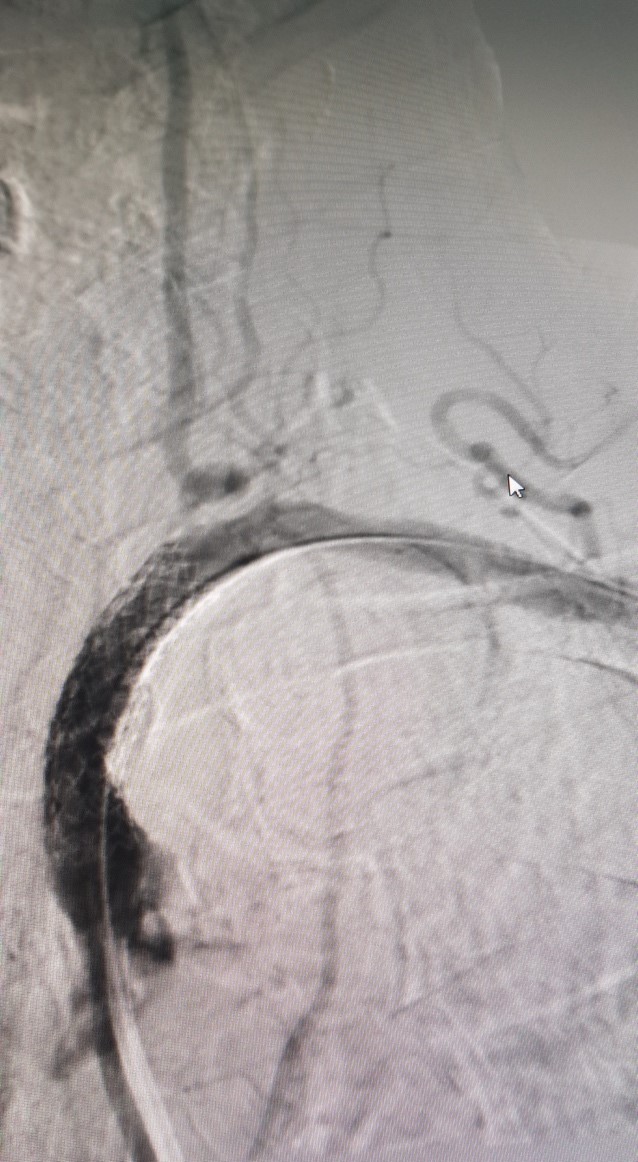

Trước can thiệp

Hình ảnh can thiệp động mạch dưới đòn tại Bệnh viện Đa khoa Tỉnh Quảng Trị